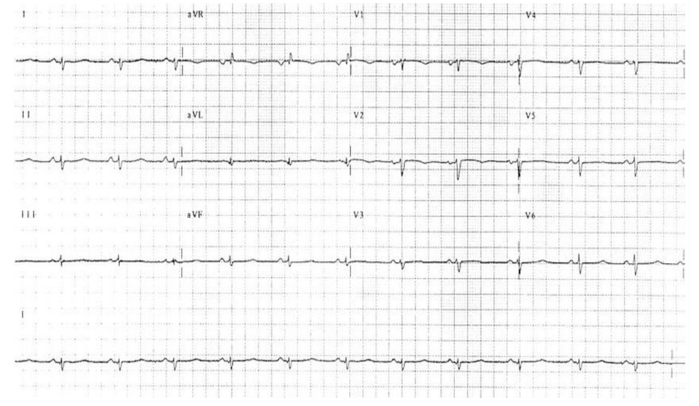

Homem de 62 anos, refere há 4 meses cansaço aos esforços, edema de membros inferiores e dispneia paroxística noturna. Nega dor

torácica, hipertensão arterial, diabetes, tabagismo ou história familiar de cardiopatia. Relata também perda ponderal de 8 kg no período,

parestesia nos membros inferiores e tonteira frequente, principalmente ao levantar.

Ao exame: eupneico em ar ambiente, hipocorado, acianótico, afebril. Frequência cardíaca: 80 bpm; pressão arterial: 96x52 mmHg; ausculta

respiratória com crepitação bibasal, ritmo cardíaco regular, em 3 tempos (B4), bulhas normofonéticas, sem sopros. Turgência jugular

patológica a 90º. Abdome com fígado a 10 cm do rebordo costal direito, doloroso (hepatimetria 16 cm). Membros inferiores com edema

bilateral com cacifo 2+/4+ e hipoestesia ao exame neurológico. Fundoscopia sem alterações. Seu eletrocardiograma está abaixo.

Considerando este resultado e de acordo com o algoritmo de investigação não-invasiva da doença, o exame de imagem mais indicado para orientar o diagnóstico do subtipo etiológico seria a(o)